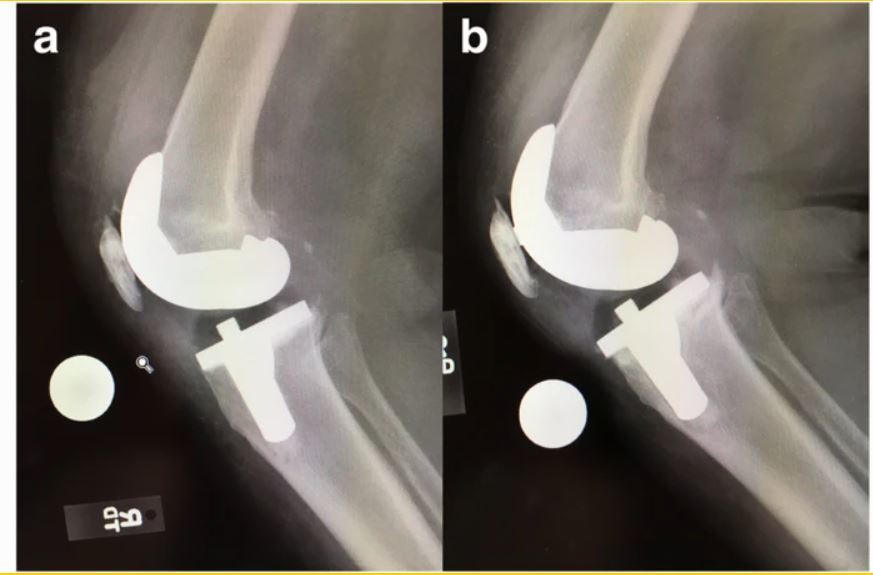

Q

Patient had undergone right knee TKA 12 years ago, now complaining of sudden onset pain at the operated knee on ambulation. This is the plain radiograph of the symptomatic knee.

1. Describe the plain radiograph.

2. How will you investigate this patient to arrive to your clinical diagnosis?

3. What is the cause of this patient’s symptoms?

4. How will you manage this patient’s pain?

A

1. Plain radiograph

Right knee prosthesis is subluxed

Evidence of femoral and tibial osteolysis

• Tibia AP - > 2 mm radiolucent area beneath the tibial plate and cement interface.

• Femoral Lat - > 2 mm radiolucent area in the posterior condyles between femoral component and cement interface.

Change in position of implant - tibial component has flexed and varus subsidence.

** cement cracking/fragmentation and delamination

1. IX - ESR and CRP to rule out infection

Clinically- afebrile, no local signs of infection (erythema, warmth, tenderness), only minimal pain on ROM and increased pain on weight bearing.

1. Aseptic loosening of TKA prosthesis

2. Revision TKA

if bone defects > 10 mm

+ prosthetic metal wedges/augments (if elderly, inactive)

+bone graft (younger patients, active)

Re picture attached:

The classic loosening of the implant in worst instances begins with a delamination pull-away of the cement on the posterior keel, followed by failure of the proximal posterior tibial surfaces; Compare the positioning immediately post-op (a) verses that at 6 months, where the slope changes from 7o to 9o and the implant subsides (b)